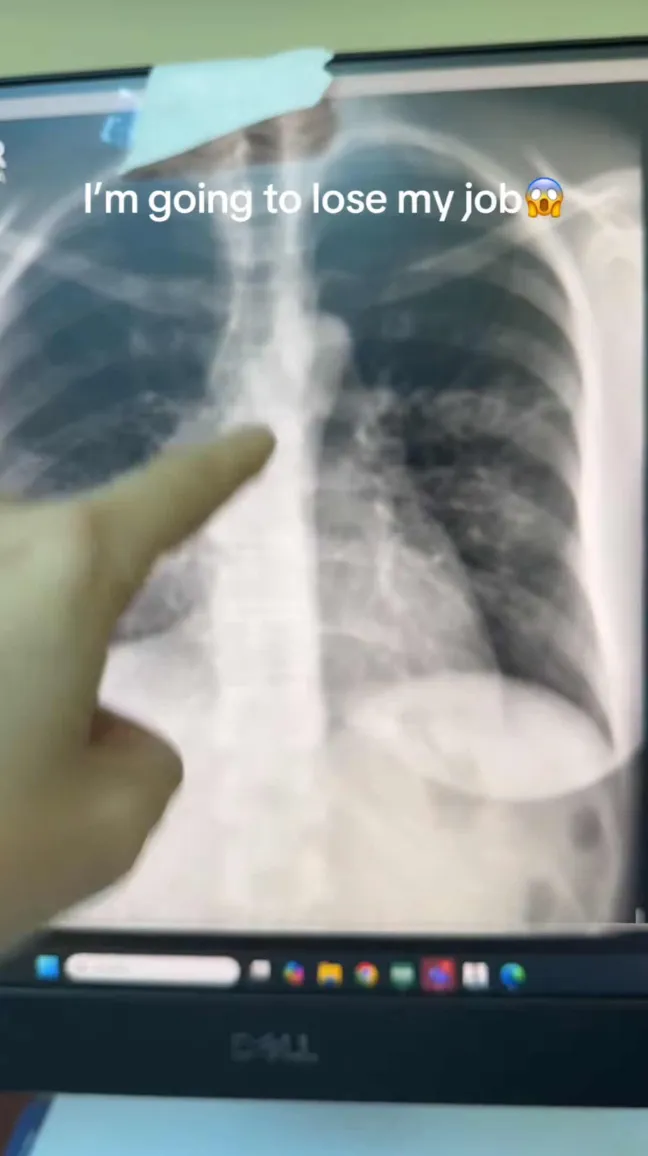

In a TikTok video, @dr.fawzikatranji, a seasoned pulmonologist, showed a comparison of a patient’s chest X-ray followed by an AI-analyzed version.

He said, "So I'm about to lose my job. And this is scary because I developed a skill over 20 years." He narrated how he could instantly identify patterns in an X-ray.

He said of the example X-ray, "We have right middle lobe pneumonia, maybe left upper lobe consolidation. Patient is very sick. She has bilateral pneumonia. We need to take care of her."

However, AI’s rapid and accurate read shook him. "Here comes AI," the doctor said, "and of course, they pick it up in a second."

The AI flagged pneumonia almost instantly, leaving the doctor wondering aloud about his future. "So now you don't need professional eyes to look at these X-rays... I’m gonna be applying to McDonald's soon. I hope they have some openings."